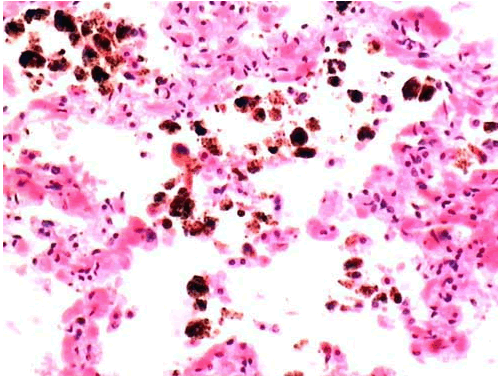

B含铁血黄素

C陈旧性出血